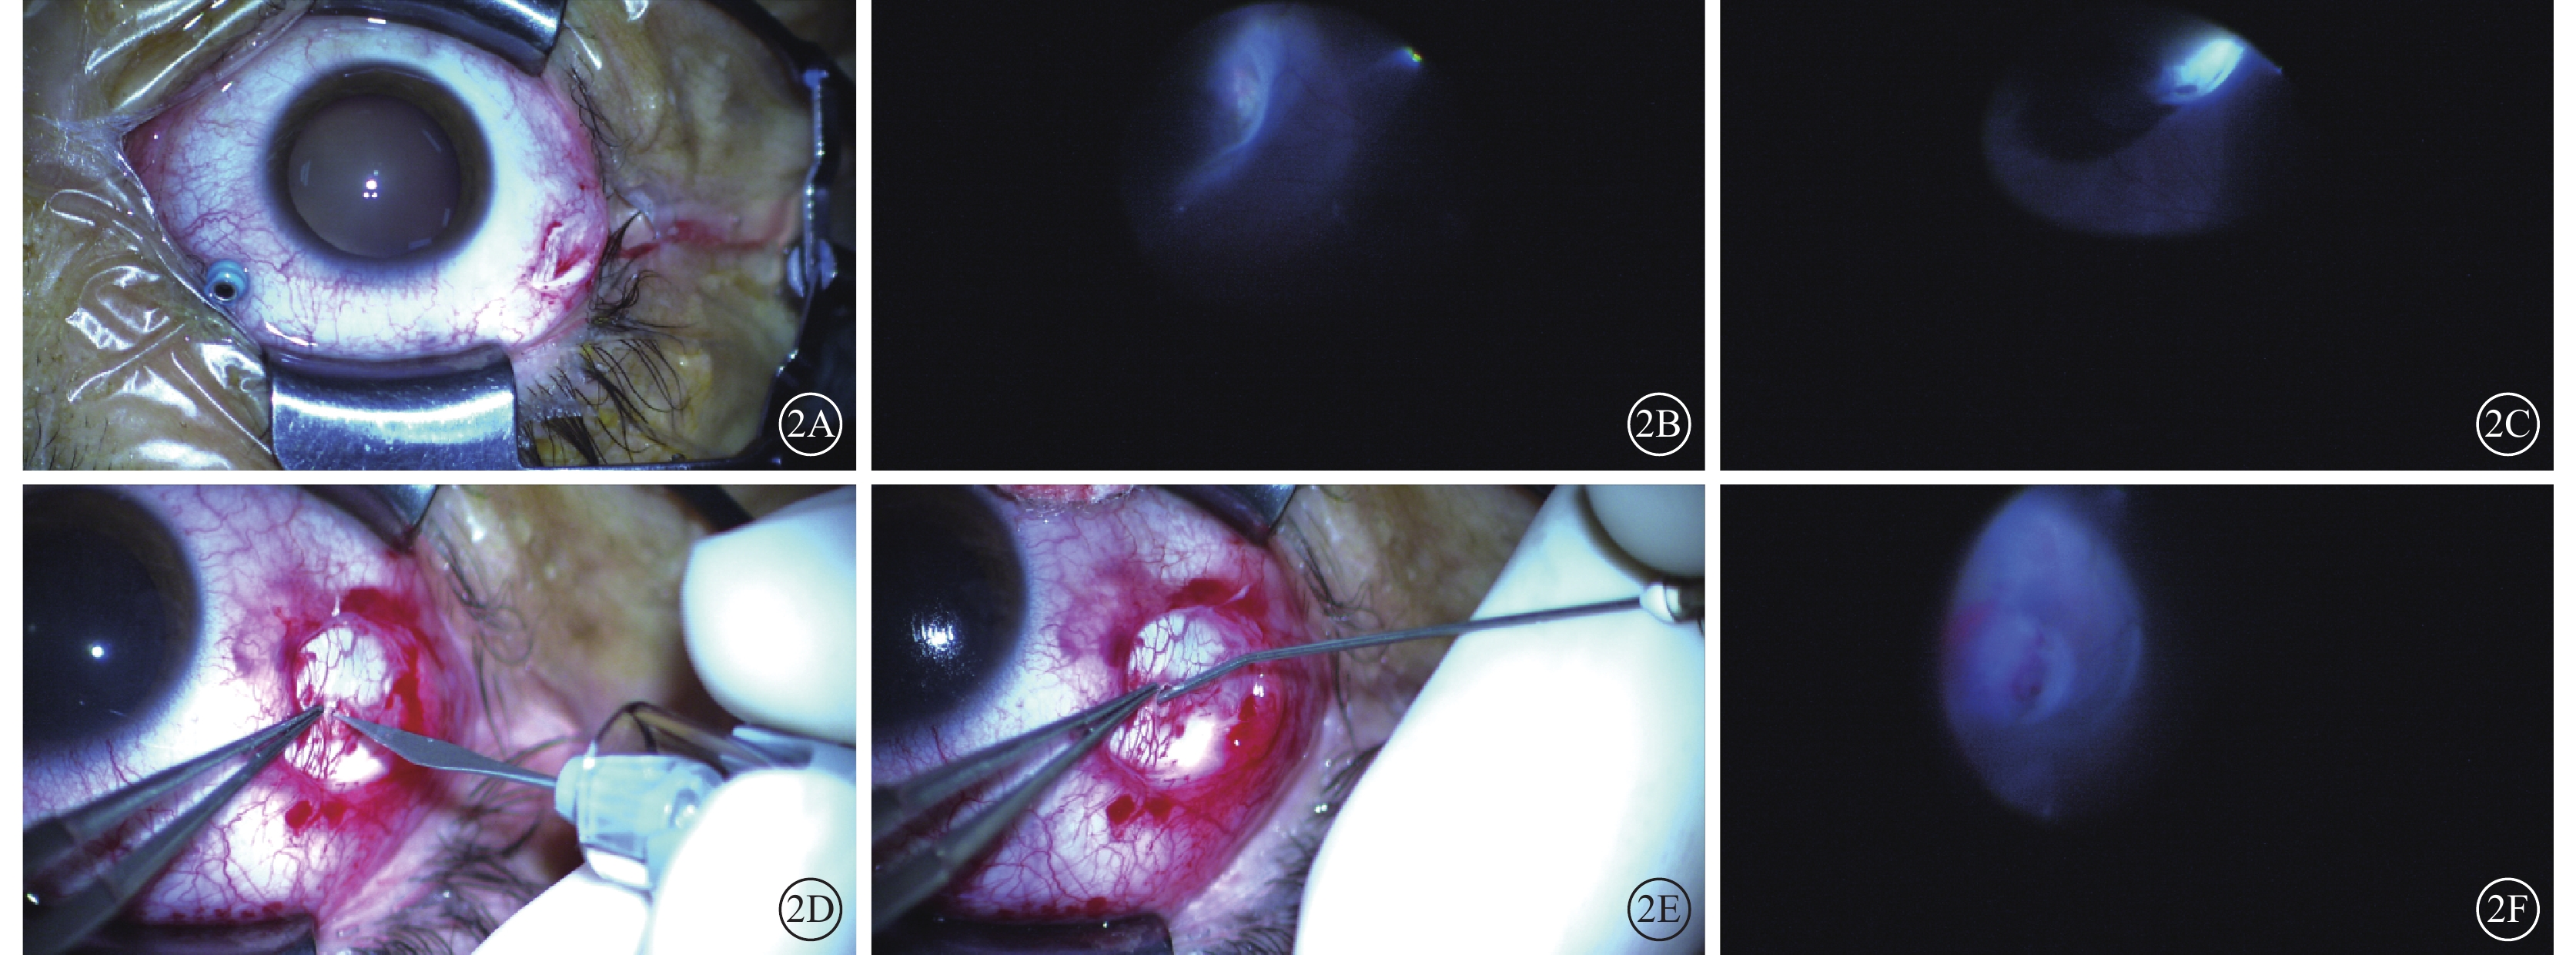

所有患眼在廣域顯微鏡帶內照明系統輔助下行脈絡膜上腔注射透明質酸鈉墊壓手術。手術均由同一位具有豐富手術經驗的醫師完成。患眼經2%利多卡因球后麻醉,在手術顯微鏡下于睫狀體平坦部距角鞏膜緣3.5 mm處并避開裂孔所在象限穿刺25G套管(圖2A),插入光纖照明,放置非接觸廣角系統,仔細檢查全視網膜,尋找視網膜裂孔及變性區(圖2B)并進行定位。對應視網膜裂孔處先行鞏膜外冷凍(圖2C),再根據視網膜脫離隆起較高區域選擇放液部位穿刺放出適量視網膜下液;在裂孔所在象限于兩條直肌之間,距角鞏膜緣6~8 mm處做4~6 mm結膜小切口,分離Tenon’s囊暴露其下鞏膜,做1~2 mm鞏膜板層小切口,分離剩余板層鞏膜(圖2D)。待恰巧穿透鞏膜后,應用自帶鈍性針頭將醫用透明質酸鈉凝膠(德國Bausch Lomb公司)置入鞏膜下、脈絡膜上腔(圖2E)。在顯微鏡直視下緩慢將透明質酸鈉推注入脈絡膜上腔,待顯微鏡下觀察到脈絡膜形成局限性嵴樣隆起并確認視網膜裂孔位于該嵴上(圖2F)后拔出鈍性針頭,8-0可吸收線縫合鞏膜切口及結膜切口各1針。再次在顯微鏡直視下檢查視網膜,必要時對裂孔再行激光光凝以加固裂孔周圍視網膜,最后拔出鞏膜穿刺套管。手術結束后囑患者向裂孔方側臥休息2周,確保裂孔始終呈低位。手術后1周內根據復查情況安排患者行視網膜激光光凝進一步加固裂孔周圍視網膜。

圖2

手術操作圖。2A示于睫狀體平坦部距角鞏膜緣3.5 mm處穿刺25G套管;2B示顯微鏡下檢查全視網膜,定位視網膜裂孔;2C示顯微鏡下對視網膜裂孔行鞏膜外冷凍;2D示在視網膜裂孔區域做2 mm鞏膜板層切口,分離剩余板層鞏膜;2E示通過自帶鈍性針頭將醫用透明質酸鈉凝膠置入鞏膜下及脈絡膜上腔;2F示顯微鏡下確認脈絡膜形成局限性嵴樣隆起且視網膜裂孔位于該嵴上

圖2

手術操作圖。2A示于睫狀體平坦部距角鞏膜緣3.5 mm處穿刺25G套管;2B示顯微鏡下檢查全視網膜,定位視網膜裂孔;2C示顯微鏡下對視網膜裂孔行鞏膜外冷凍;2D示在視網膜裂孔區域做2 mm鞏膜板層切口,分離剩余板層鞏膜;2E示通過自帶鈍性針頭將醫用透明質酸鈉凝膠置入鞏膜下及脈絡膜上腔;2F示顯微鏡下確認脈絡膜形成局限性嵴樣隆起且視網膜裂孔位于該嵴上

所有患眼在廣域顯微鏡帶內照明系統輔助下行脈絡膜上腔注射透明質酸鈉墊壓手術。手術均由同一位具有豐富手術經驗的醫師完成。患眼經2%利多卡因球后麻醉,在手術顯微鏡下于睫狀體平坦部距角鞏膜緣3.5 mm處并避開裂孔所在象限穿刺25G套管(圖2A),插入光纖照明,放置非接觸廣角系統,仔細檢查全視網膜,尋找視網膜裂孔及變性區(圖2B)并進行定位。對應視網膜裂孔處先行鞏膜外冷凍(圖2C),再根據視網膜脫離隆起較高區域選擇放液部位穿刺放出適量視網膜下液;在裂孔所在象限于兩條直肌之間,距角鞏膜緣6~8 mm處做4~6 mm結膜小切口,分離Tenon’s囊暴露其下鞏膜,做1~2 mm鞏膜板層小切口,分離剩余板層鞏膜(圖2D)。待恰巧穿透鞏膜后,應用自帶鈍性針頭將醫用透明質酸鈉凝膠(德國Bausch Lomb公司)置入鞏膜下、脈絡膜上腔(圖2E)。在顯微鏡直視下緩慢將透明質酸鈉推注入脈絡膜上腔,待顯微鏡下觀察到脈絡膜形成局限性嵴樣隆起并確認視網膜裂孔位于該嵴上(圖2F)后拔出鈍性針頭,8-0可吸收線縫合鞏膜切口及結膜切口各1針。再次在顯微鏡直視下檢查視網膜,必要時對裂孔再行激光光凝以加固裂孔周圍視網膜,最后拔出鞏膜穿刺套管。手術結束后囑患者向裂孔方側臥休息2周,確保裂孔始終呈低位。手術后1周內根據復查情況安排患者行視網膜激光光凝進一步加固裂孔周圍視網膜。

圖2

手術操作圖。2A示于睫狀體平坦部距角鞏膜緣3.5 mm處穿刺25G套管;2B示顯微鏡下檢查全視網膜,定位視網膜裂孔;2C示顯微鏡下對視網膜裂孔行鞏膜外冷凍;2D示在視網膜裂孔區域做2 mm鞏膜板層切口,分離剩余板層鞏膜;2E示通過自帶鈍性針頭將醫用透明質酸鈉凝膠置入鞏膜下及脈絡膜上腔;2F示顯微鏡下確認脈絡膜形成局限性嵴樣隆起且視網膜裂孔位于該嵴上

圖2

手術操作圖。2A示于睫狀體平坦部距角鞏膜緣3.5 mm處穿刺25G套管;2B示顯微鏡下檢查全視網膜,定位視網膜裂孔;2C示顯微鏡下對視網膜裂孔行鞏膜外冷凍;2D示在視網膜裂孔區域做2 mm鞏膜板層切口,分離剩余板層鞏膜;2E示通過自帶鈍性針頭將醫用透明質酸鈉凝膠置入鞏膜下及脈絡膜上腔;2F示顯微鏡下確認脈絡膜形成局限性嵴樣隆起且視網膜裂孔位于該嵴上